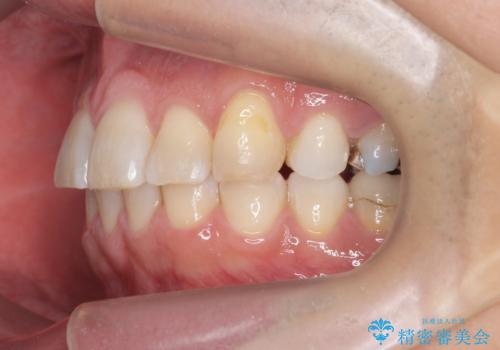

治療終了後、治療前後の写真をお見せすると「全然違いますね!」と喜んで下さいました。

実際の矯正期間は3ヶ月2週間(マウスピース14枚、1週間交換)と短期間で治療を終えることができました。